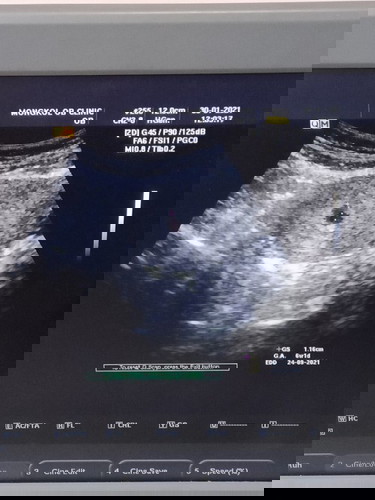

พอดีตรวจพบว่าท้องแล้วไปฝากครรภ์ อัลตร้าซาวด์ พบถุงตั้งครรภ์ แต่ไม่เห็นหัวใจเด็กเต้น หรือว่าอายุครรภ์ ยังน้อยไปค่ะ เพิ่งจะ6w